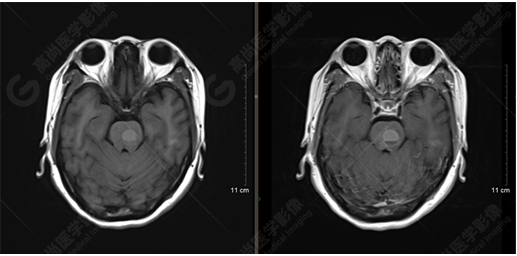

T1WI及T1增強序列

影像表現(xiàn):橋腦見一類圓形異常信號影,直徑約1.3cm,呈T1WI稍高信號,T2WI及FLAIR序列高信號,其內(nèi)見高低信號分層,增強后無明顯強化。大腦鐮前部旁見兩個結(jié)節(jié)影,較大者直徑約1.4cm,呈各序列等信號,增強后呈均勻明顯強化,鄰近大腦鐮增厚、強化。右側(cè)額葉腦白質(zhì)內(nèi)見一斑點狀等T1長T2信號影,F(xiàn)LAIR序列呈高信號,增強后無強化;余腦實質(zhì)內(nèi)未見局灶性信號異常,增強后未見異常強化。各腦室、腦池大小、形態(tài)均正常,中線結(jié)構(gòu)居中,幕下小腦無異常。矢狀面示垂體大小形態(tài)正常,未見局灶性信號異常。